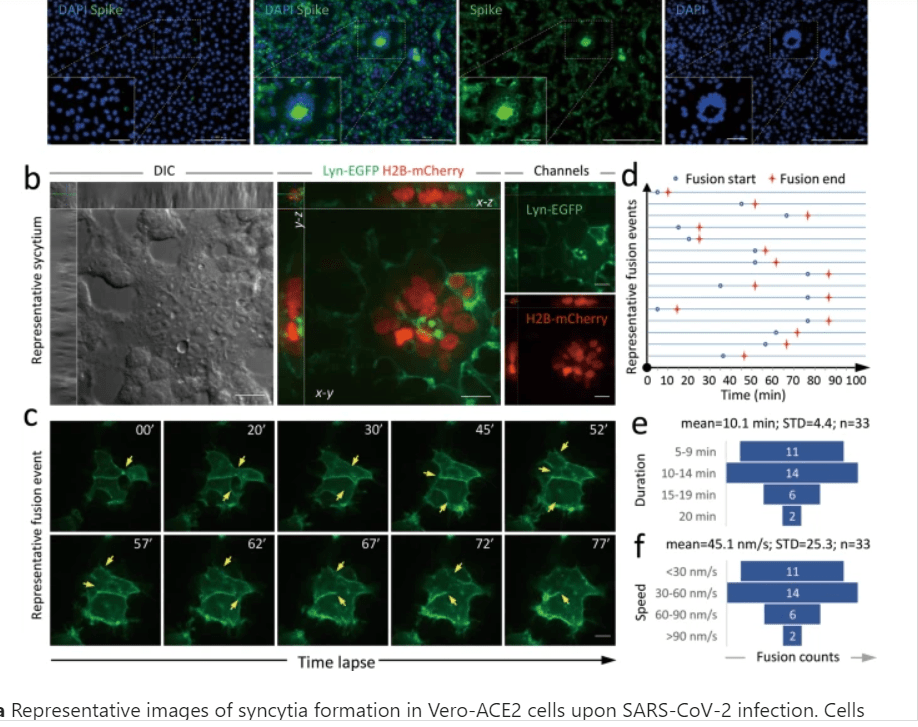

Cette belle vidéo montre la fusion cellulaire en temps réel aboutissant à la formation des syncytia. La cellule verte exprime la spike à sa surface et la cellule violette exprime ACE2

La formation des syncytia est due à l’interaction entre

-la Spike exprimée à la surface de la cellule infectée et

-le récepteur ACE2/TMPRSS2 exprimé à la surface des cellules non-infectées

Cette propriété à produire des syncytia est reconnue comme jouant un rôle dans la virulence.

Omicron, moins virulent sur le terrain, est quasi incapable de produire des syncytia sans doute à cause des mutations accumulées dans sa spike

Dans cette publi, des lignées cellulaires exprimant la spike « omicron » ne forment pratiquement pas de syncytia